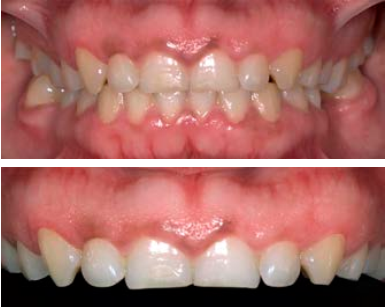

Se revisó a la paciente tras haber realizar el procedimiento quirúrgico, no presentó ninguna complicación, los tejidos gingivales con características normales, sin procesos inflamatorios y acorde con el proceso de cicatrización (Figura 5).